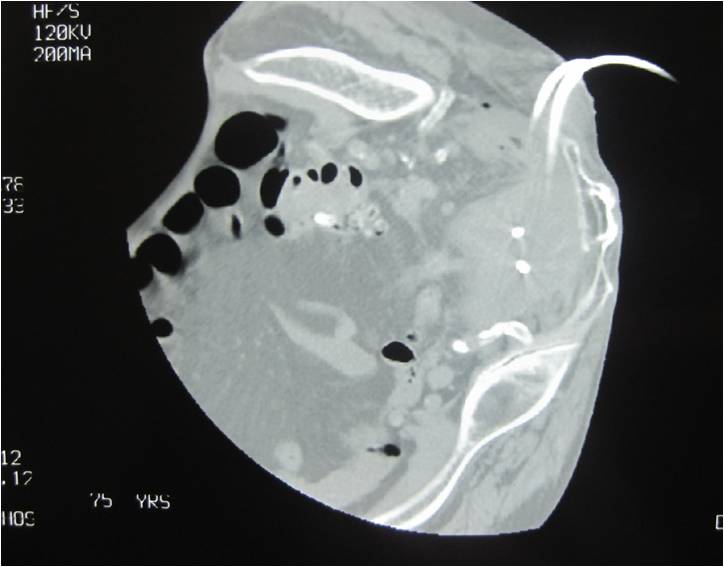

- Large abdominal abscess post- pancreatic surgery

- Successful drainage